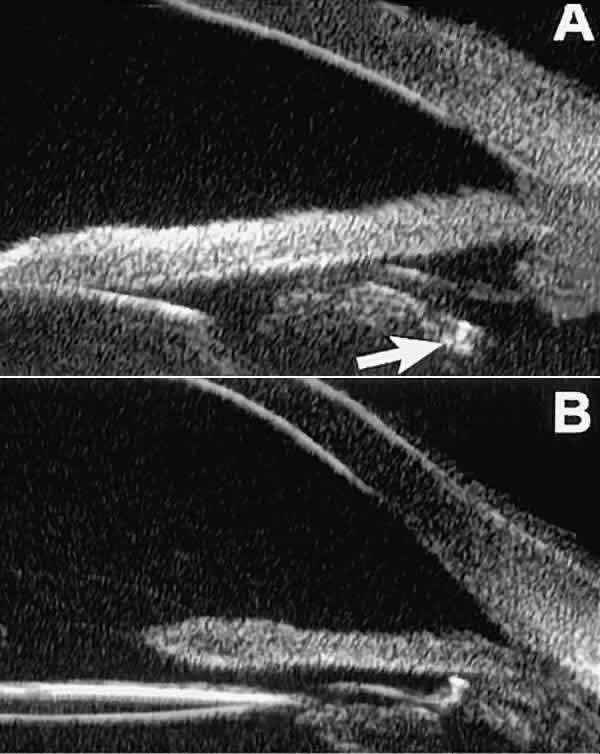

The role of UBM in the preoperative assessment of eyes with cataract is as yet unknown. In certain eyes, however, UBM may reveal features or abnormalities that could alter the ophthalmologist's surgical approach. Postoperatively, UBM can show the size and location of an intraocular lens (IOL) and the positioning of the haptics. A posterior chamber IOL appears on UBM as a highly reflective plate (corresponding to the lens optic) in the retropupillary plane with reverberation artifacts behind it (Fig. 17A). In contrast, an anterior chamber IOL appears on UBM as a sonoreflective plate located anterior to the pupillary plane (see Fig. 17B). In most eyes with a posterior chamber IOL, UBM can show whether the haptics are in the capsular bag (Fig. 18A), in the ciliary sulcus (see Fig. 18B), or in some other anatomic location12 (e.g., resting on the peripheral iris or secured with sutures to the sclera). The haptics are easier to locate if they are made of polymethyl-methacrylate than if they are made of proline because the former has a stronger reflectance.

Fig. 17. Composite UBM images of intraocular lenses. A. Posterior chamber IOL. B. Anterior chamber IOL.

Fig. 18 . Localization of posterior chamber IOL haptics by UBM. A. Haptic in capsular bag (arrow). B. Haptic (bright object just behind peripheral iris) in iridociliary sulcus.